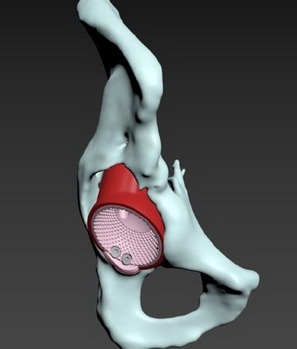

Приклад заміщення дефектів кісток тазу при ураженні пухлиною. Складне індивідуальне ендопротезування кульшового суглоба

Розрахунок розміру компонента, імплантація ревізійної ацетабулярної системи, Розмір трансплантованої кістки з використанням опорних площ, доповнюючи масивною кістковою пластикою дефектів з метою відновлення рекомендованої позиції компонента

Операція: Вилучення металофіксаотора. Повна артропластика лівого кульшового суглоба з індивідуальним ацетабулярним компонентом

Спроектована та імплантована індивідуальна, пориста, титанова, 3D-друкована кульшова западина, фіксована гвинтами.